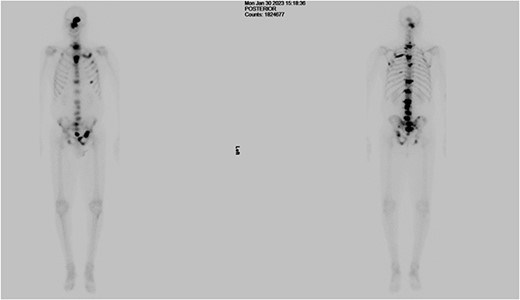

The patient was then referred to the urology department by the Head & Neck MDT. As part of his workup, a digital rectal examination (DRE), PSA test, prostate biopsy, and bone scan were recommended, and gonadotropin-releasing hormone (GnRH) antagonists were started. The DRE revealed a mildly enlarged, firm, smooth prostate with no nodularity. The PSA level was 1271 ng/dl, which decreased to 639 g/L within 1 week of the commencement of treatment. Transrectal ultrasound revealed a prostate volume of 54 cc and a local anaesthetic transperineal template biopsy of the prostate revealed prostatic adenocarcinoma with 4 out of 12 cores from the right gland with a Gleason Score of 4 + 5 and 1 out of 12 cores from the left gland with a Gleason Score of 5 + 5. The mean overall Gleason score was 5. Additional features included a cribriform pattern and perineural invasion (Fig. 3). Bone scans revealed multiple areas of increased tracer uptake, including the skull vault and skull base, cervical spine, thoracic spine, lumbar spine, and pelvis, with multiple bony metastases (Fig. 4). Therefore, the staging of the disease was T1c N0 M1b, high-risk, or Cambridge Prognostic Group 5.

Bone scan showing multiple areas of increased tracer uptake, including the skull vault and skull base, cervical spine, thoracic spine, lumbar spine, and pelvis, revealing multiple bony metastases.